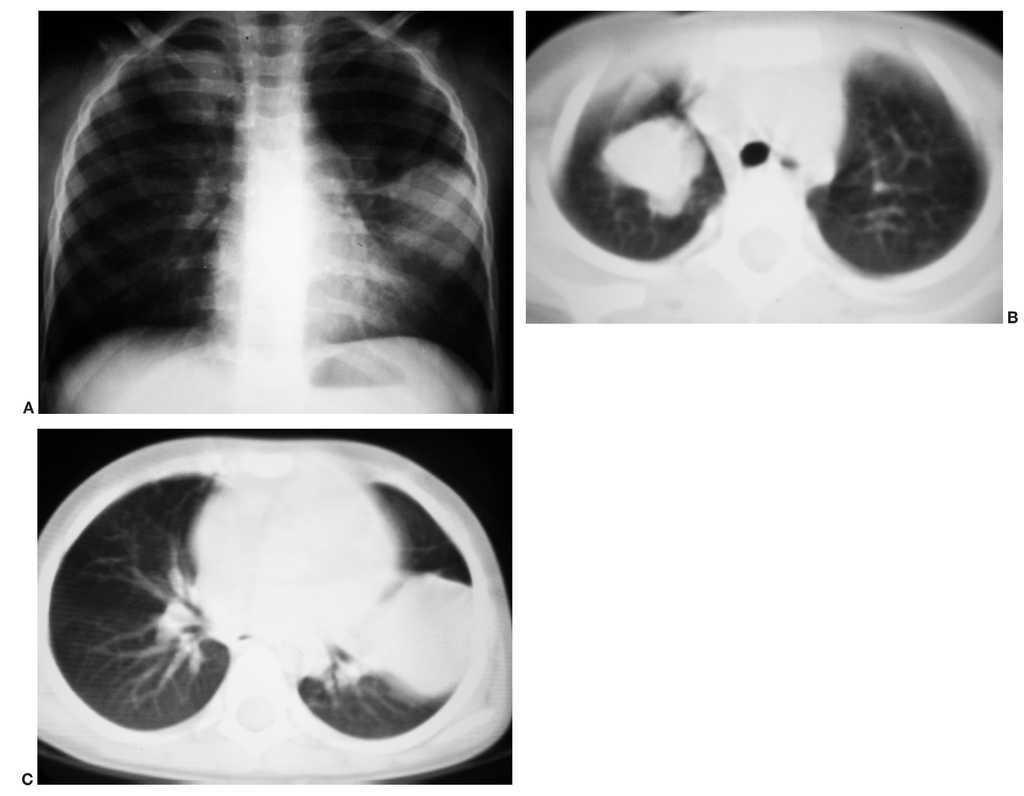

Presentamos el caso de un niño de 20 meses con antecedentes de prematuridad y enfermedad de membrana hialina, que comienza con disnea y mal estado general. En la radiografía torácica se observa una opacificación del hemitórax izquierdo por derrame pleural masivo (fig. 3A). Tras realizar un drenaje pleural se extraen 500 ml de líquido hemático. Se le realiza una TC en la que se observa una gran masa torácica paravertebral izquierda, sólida, polilobulada, con extensión desde D3 a D10, y con semiología radiológica de lesión extrapulmonar que depende fundamentalmente de la pleura. Presenta un patrón de captación discreto y homogéneo, y no muestra signos de afectación del canal raquídeo ni de la pared torácica (fig. 3B). Se realiza biopsia de la lesión con diagnóstico histológico de tumor de células azules, redondas y pequeñas, con diferenciación muscular, compatible con BPP tipo III. La evolución es tórpida, a pesar del tratamiento con quimioterapia y tres intervenciones quirúrgicas. En la RM de control se observa un engrosamiento pleural difuso metastásico en el hemitórax izquierdo (figs. 3C y 3D). La afectación tumoral prosigue, presentando finalmente un colapso pulmonar, invasión mediastínica y de pared torácica anterior, metástasis orbitarias y diseminación abdominal. Fallece a los dos años del diagnóstico.

Fig. 3. Caso 3. (A) Radiografía inicial. Derrame pleural izquierdo masivo y desplazamiento mediastínico contralateral. (B) Tomografía computarizada de tórax con contraste tras drenaje del derrame pleural; corte axial. Masa extrapulmonar paravertebral izquierda, dependiente de pleura, con lesiones nodulares en cavidad pleural (flechas) y sin extensión al canal medular ni afectación de pared costal. Resonancia magnética en secuencias T1 + Gd (C) y T2 (D). Engrosamiento pleural difuso metástasico en el hemitórax izquierdo con varias masas, una en el ápex pulmonar izquierdo con extensión al mediastino anterosuperior y que abomba la pared torácica anterior (1), otra paravertebral izquierda (2) y la tercera en el seno costofrénico anterior izquierdo (3).